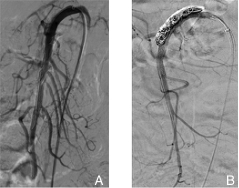

图1 SISMAD分型 A:Ⅰ型;B:Ⅱa型;C:Ⅱb型;D:Ⅲ型Fig.1 SISMAD classification A: TypeⅠ; B: Type Ⅱa; C: Type Ⅱb; D: Type Ⅲ